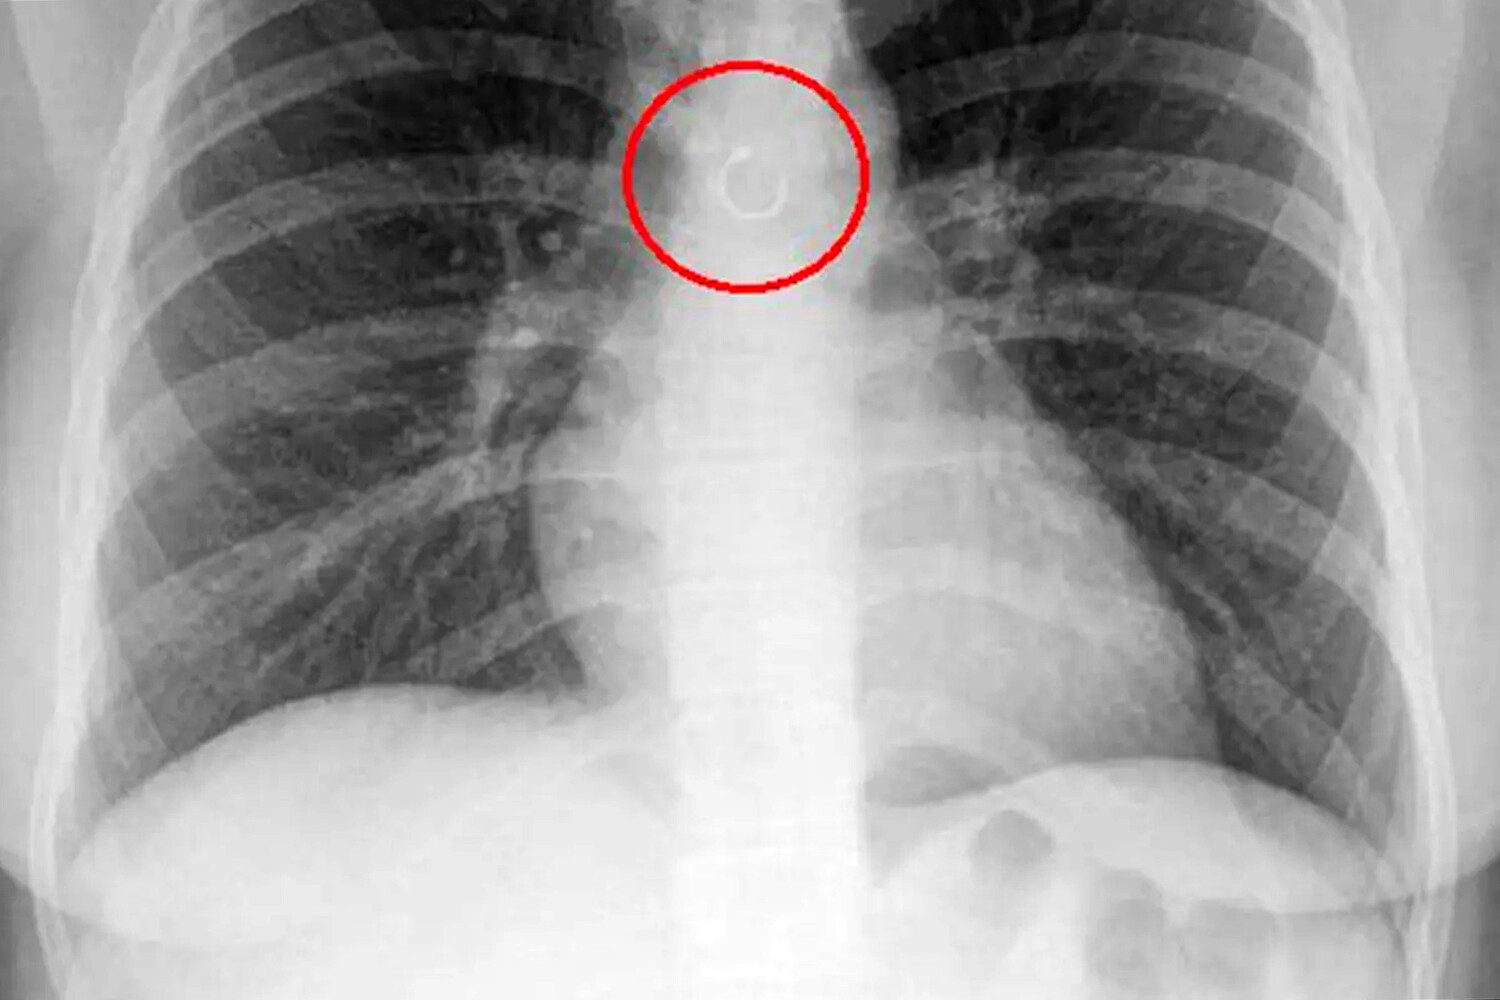

Во время обследования выяснилось, что украшение из пирсинга в носу каким-то образом оказалось глубоко в дыхательных путях девушки и застряло в легких. Металлический элемент находился всего в полумиллиметре от аорты, что могло привести к опасным последствиям, добавили медики.